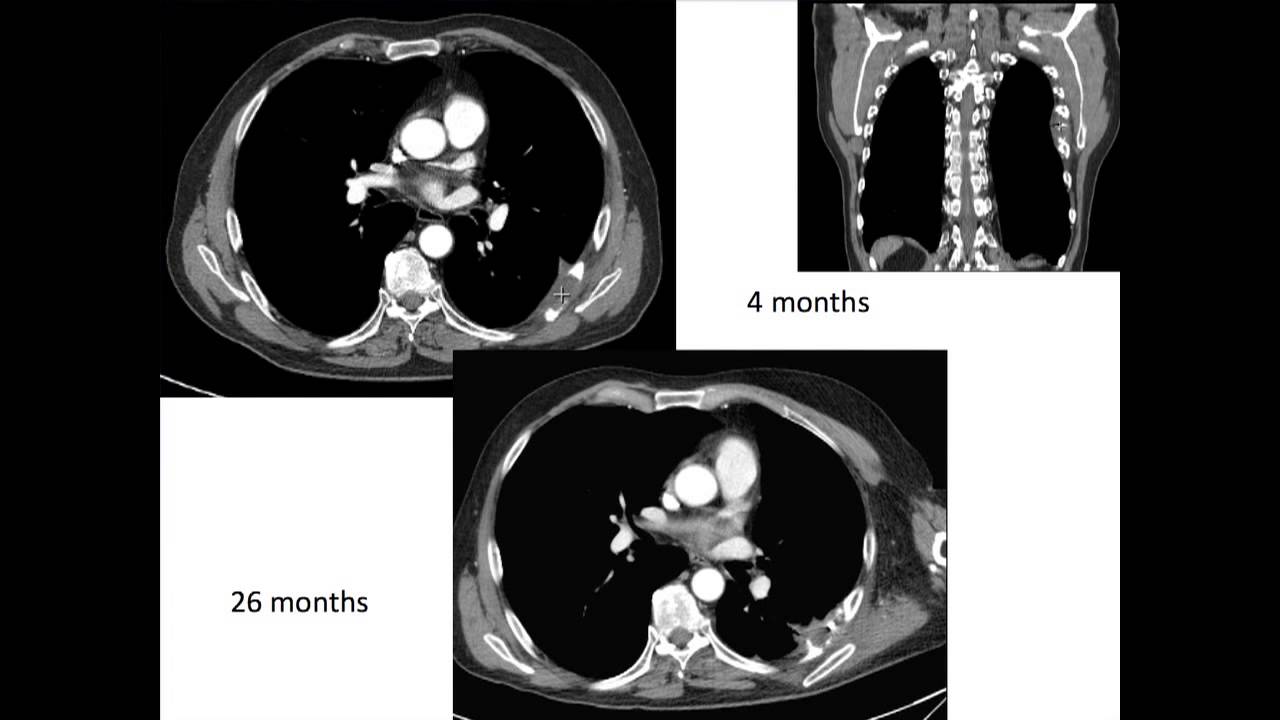

Kidney Cancer

A new treatment for kidney cancer on the horizon?